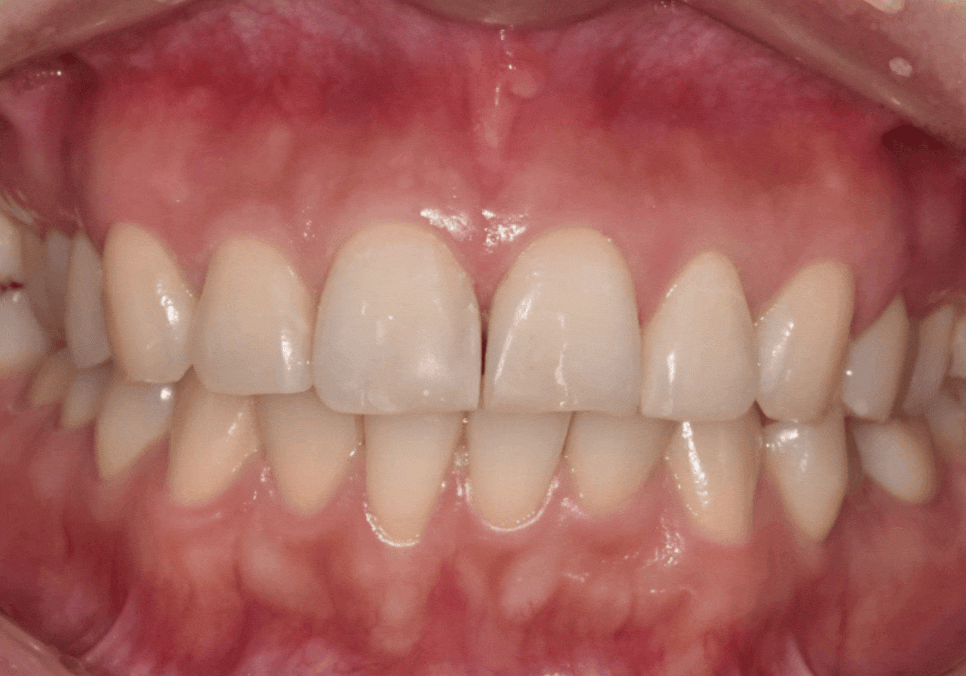

이 환자분은 예전에

앞니 사이가 벌어져 보여서

레진으로 공간을 메우는 치료를 받으셨습니다.

240413